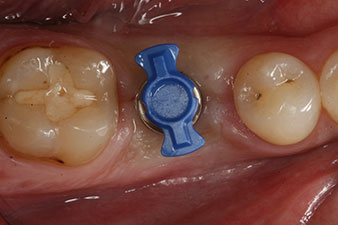

The implant was placed as planned after thorough removal of the granulation tissue (blueSky, bredent).

The torque used for the machine-driven placement was 43 Ncm. In addition, after screwing a measuring post (SmartPeg) specially matched to the implant, the ISQ value was measured with the probe of the W&H Osstell ISQ module.

This module is an optional extra for the W&H Implantmed and is docked to the implantology motor (see Fig. 11). The dimensionless ISQ value immediately after insertion was 64 orovestibular and 68 mesiodistal (maximum value = 100).